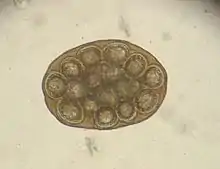

El gusano en su forma adulta mide entre 15-70 centímetros de largo por 2,5 - 3 milímetros de diámetro y tiene una coloración que varía entre el blanco y el amarillo claro. El cuerpo consta de una cabeza donde se encuentra la escólex, que mide 0,37 milímetros, gran parte de ella está compuesta por un rostelo retráctil, dotado de minúsculos ganchos, repartidos en 4-7 filas de filamentos, con los cuales el parásito se agarra a la pared intestinal del huésped definitivo. El gusano está dividido en segmentos o proglótidos, en cada proglótido se encuentran dos gónadas, masculina y femenina, por lo que los gusanos son hermafroditas. Cada individuo presenta de 60 a 175 proglótidos. Los proglótidos presentan una forma ovoidal alargada con una longitud de unos 12 milímetros por una anchura de unos 2,7 milímetros, y contiene agrupaciones de cápsulas que tienen en su interior de 25 a 30 huevos. Los huevos miden de 35-60 micras.[2]